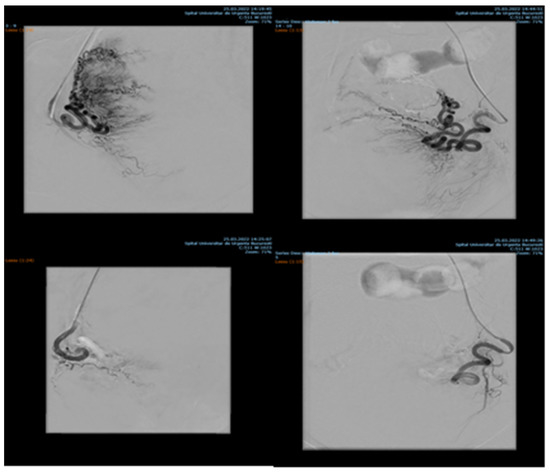

7.84% (n = 89) of the patients with cervix cancer needed supraselective embolization of cervicovaginal and long vaginal arteries, as seen in Figure 2 and Figure 3.

Figure 2. Selective artery embolization in patient with cervical neoplasia.

Figure 3. Selective long vaginal artery embolization in patient with cervical neoplasia.